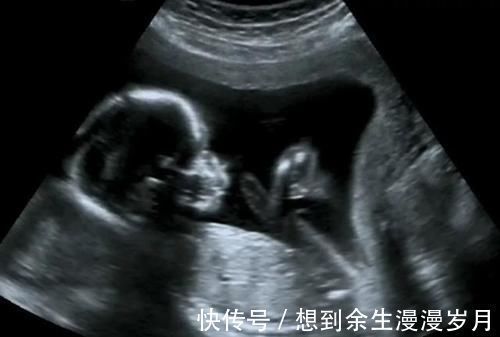

三.因为肚皮厚需要多次做超声检查或是其他检查,对胎儿有害吗?现在对于胎儿的研究表明,超声对胎儿没有影响,不会导致胎儿畸形,其原理是声波不会造成胎儿发育异常;如果选择X线或者CT,此原理来源于放射线,对于孕早期的胎儿有致畸作用,尽量避免使用,孕中期和孕晚期单次使用基本无影响;核磁共振是除彩超之外最安全的,单纯磁共振对胎儿无影响,使用造影剂对胎儿有一定致畸作用。